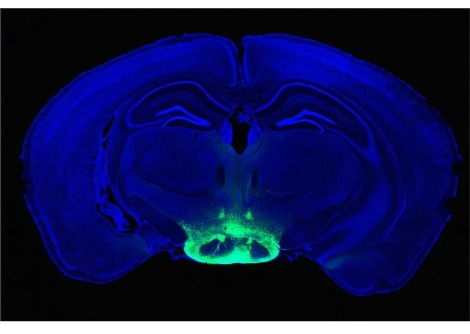

أظهرت الفئران علامات مرض الزهايمر بعد تلقي نخاع العظم من فئران أخرى تحتوي على مستويات عالية من بروتين الأميلويد المسبب في أدمغتها، لكننا بعيدون جدًا عن القول بأن الخطر ينطبق على البشر

التطور الأخير هو محاولة لتسليط الضوء على هذا السؤال من خلال البحوث الحيوانية. قام فريق من جامعة كولومبيا البريطانية في فانكوفر، كندا، بأخذ نخاع عظمي من فئران تم تعديلها وراثيا لتحتوي على مستويات عالية من الأميلويد في أدمغتها، مما يتسبب في إصابتها بمشاكل في الذاكرة في وقت مبكر من الحياة ، ثم حقنها في دم الفئران الطبيعيين. كما أصيب هؤلاء أيضًا بإعاقات إدراكية في سن مبكرة وتراكم الأميلويد في أدمغتهم .

ويقول الباحثون إن هذا يدل على أن مرض الزهايمر يمكن أن ينتقل عن طريق الإجراءات الطبية، على الأقل في الفئران. يقول تشاهات سينغ من جامعة كولومبيا البريطانية: "تنص العقيدة على أن الأميلويد المشتق من الدماغ هو الذي يؤدي إلى حالة المرض ". "هذا دليل على أن عمليات زرع نخاع العظم يمكن أن تنقل المرض بالفعل."